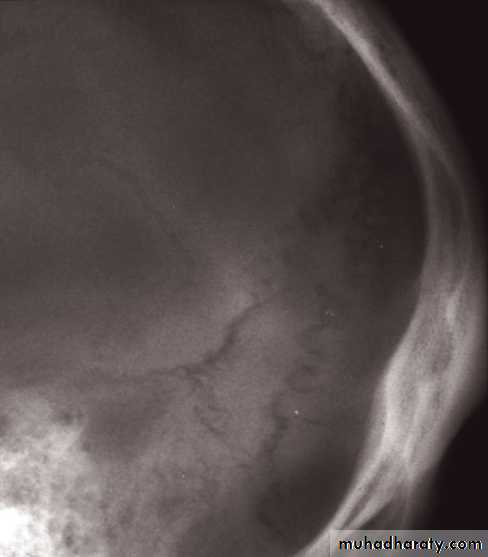

• Examination on bone windows can demonstrate fractures of the skull vault, face or skull base.

• Extradural haematoma is seen as a lens-shaped, smoothly demarcated, high-density area situated over the surface of the hemisphere associated with a skull fracture

• Fractures of the skull base or vault should be looked for on bone window settings.

• Assessment of fracture type: linear or depressed . Also assessment of Paranasal sinuses, sphenoid, petrous and occipital bones